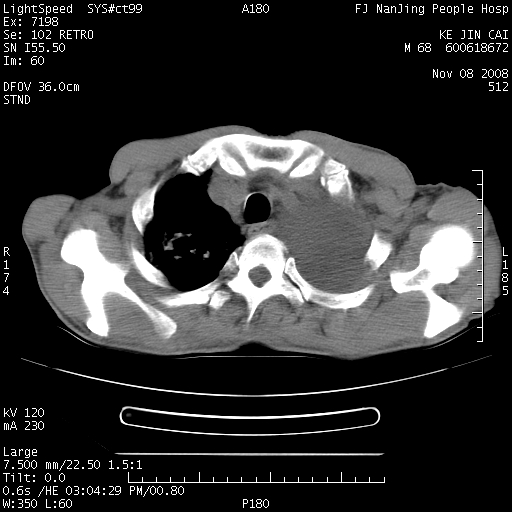

是个很有看头的病例,咋人气那么不旺?没多少人兴趣呢?这个病例几大怪:1   恶性肿瘤侵犯心肌左房怪,心肌一般不会被恶性肿瘤侵犯吧?2   左下肺均匀实变怪,内无含气,有别一般不张实变,含气肺泡完全为液体取代,而非一般不张实变的肺萎陷,冷不丁还以为是肿大的脾脏3   肿瘤本身怪,像tb肺不张4   这么有看头的病例没人气怪。呵呵。

左肺恶性肿瘤侵犯肺动脉,左心房内瘤栓,胸膜转移。

左肺恶性肿瘤侵犯肺动脉,左心房内瘤栓,胸膜转移,少见,学习了。